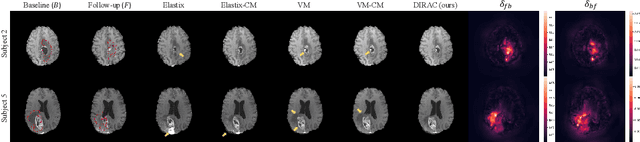

Registration of pre-operative and post-recurrence brain images is often needed to evaluate the effectiveness of brain gliomas treatment. While recent deep learning-based deformable registration methods have achieved remarkable success with healthy brain images, most of them would be unable to accurately align images with pathologies due to the absent correspondences in the reference image. In this paper, we propose a deep learning-based deformable registration method that jointly estimates regions with absent correspondence and bidirectional deformation fields. A forward-backward consistency constraint is used to aid in the localization of the resection and recurrence region from voxels with absence correspondences in the two images. Results on 3D clinical data from the BraTS-Reg challenge demonstrate our method can improve image alignment compared to traditional and deep learning-based registration approaches with or without cost function masking strategy. The source code is available at https://github.com/cwmok/DIRAC.